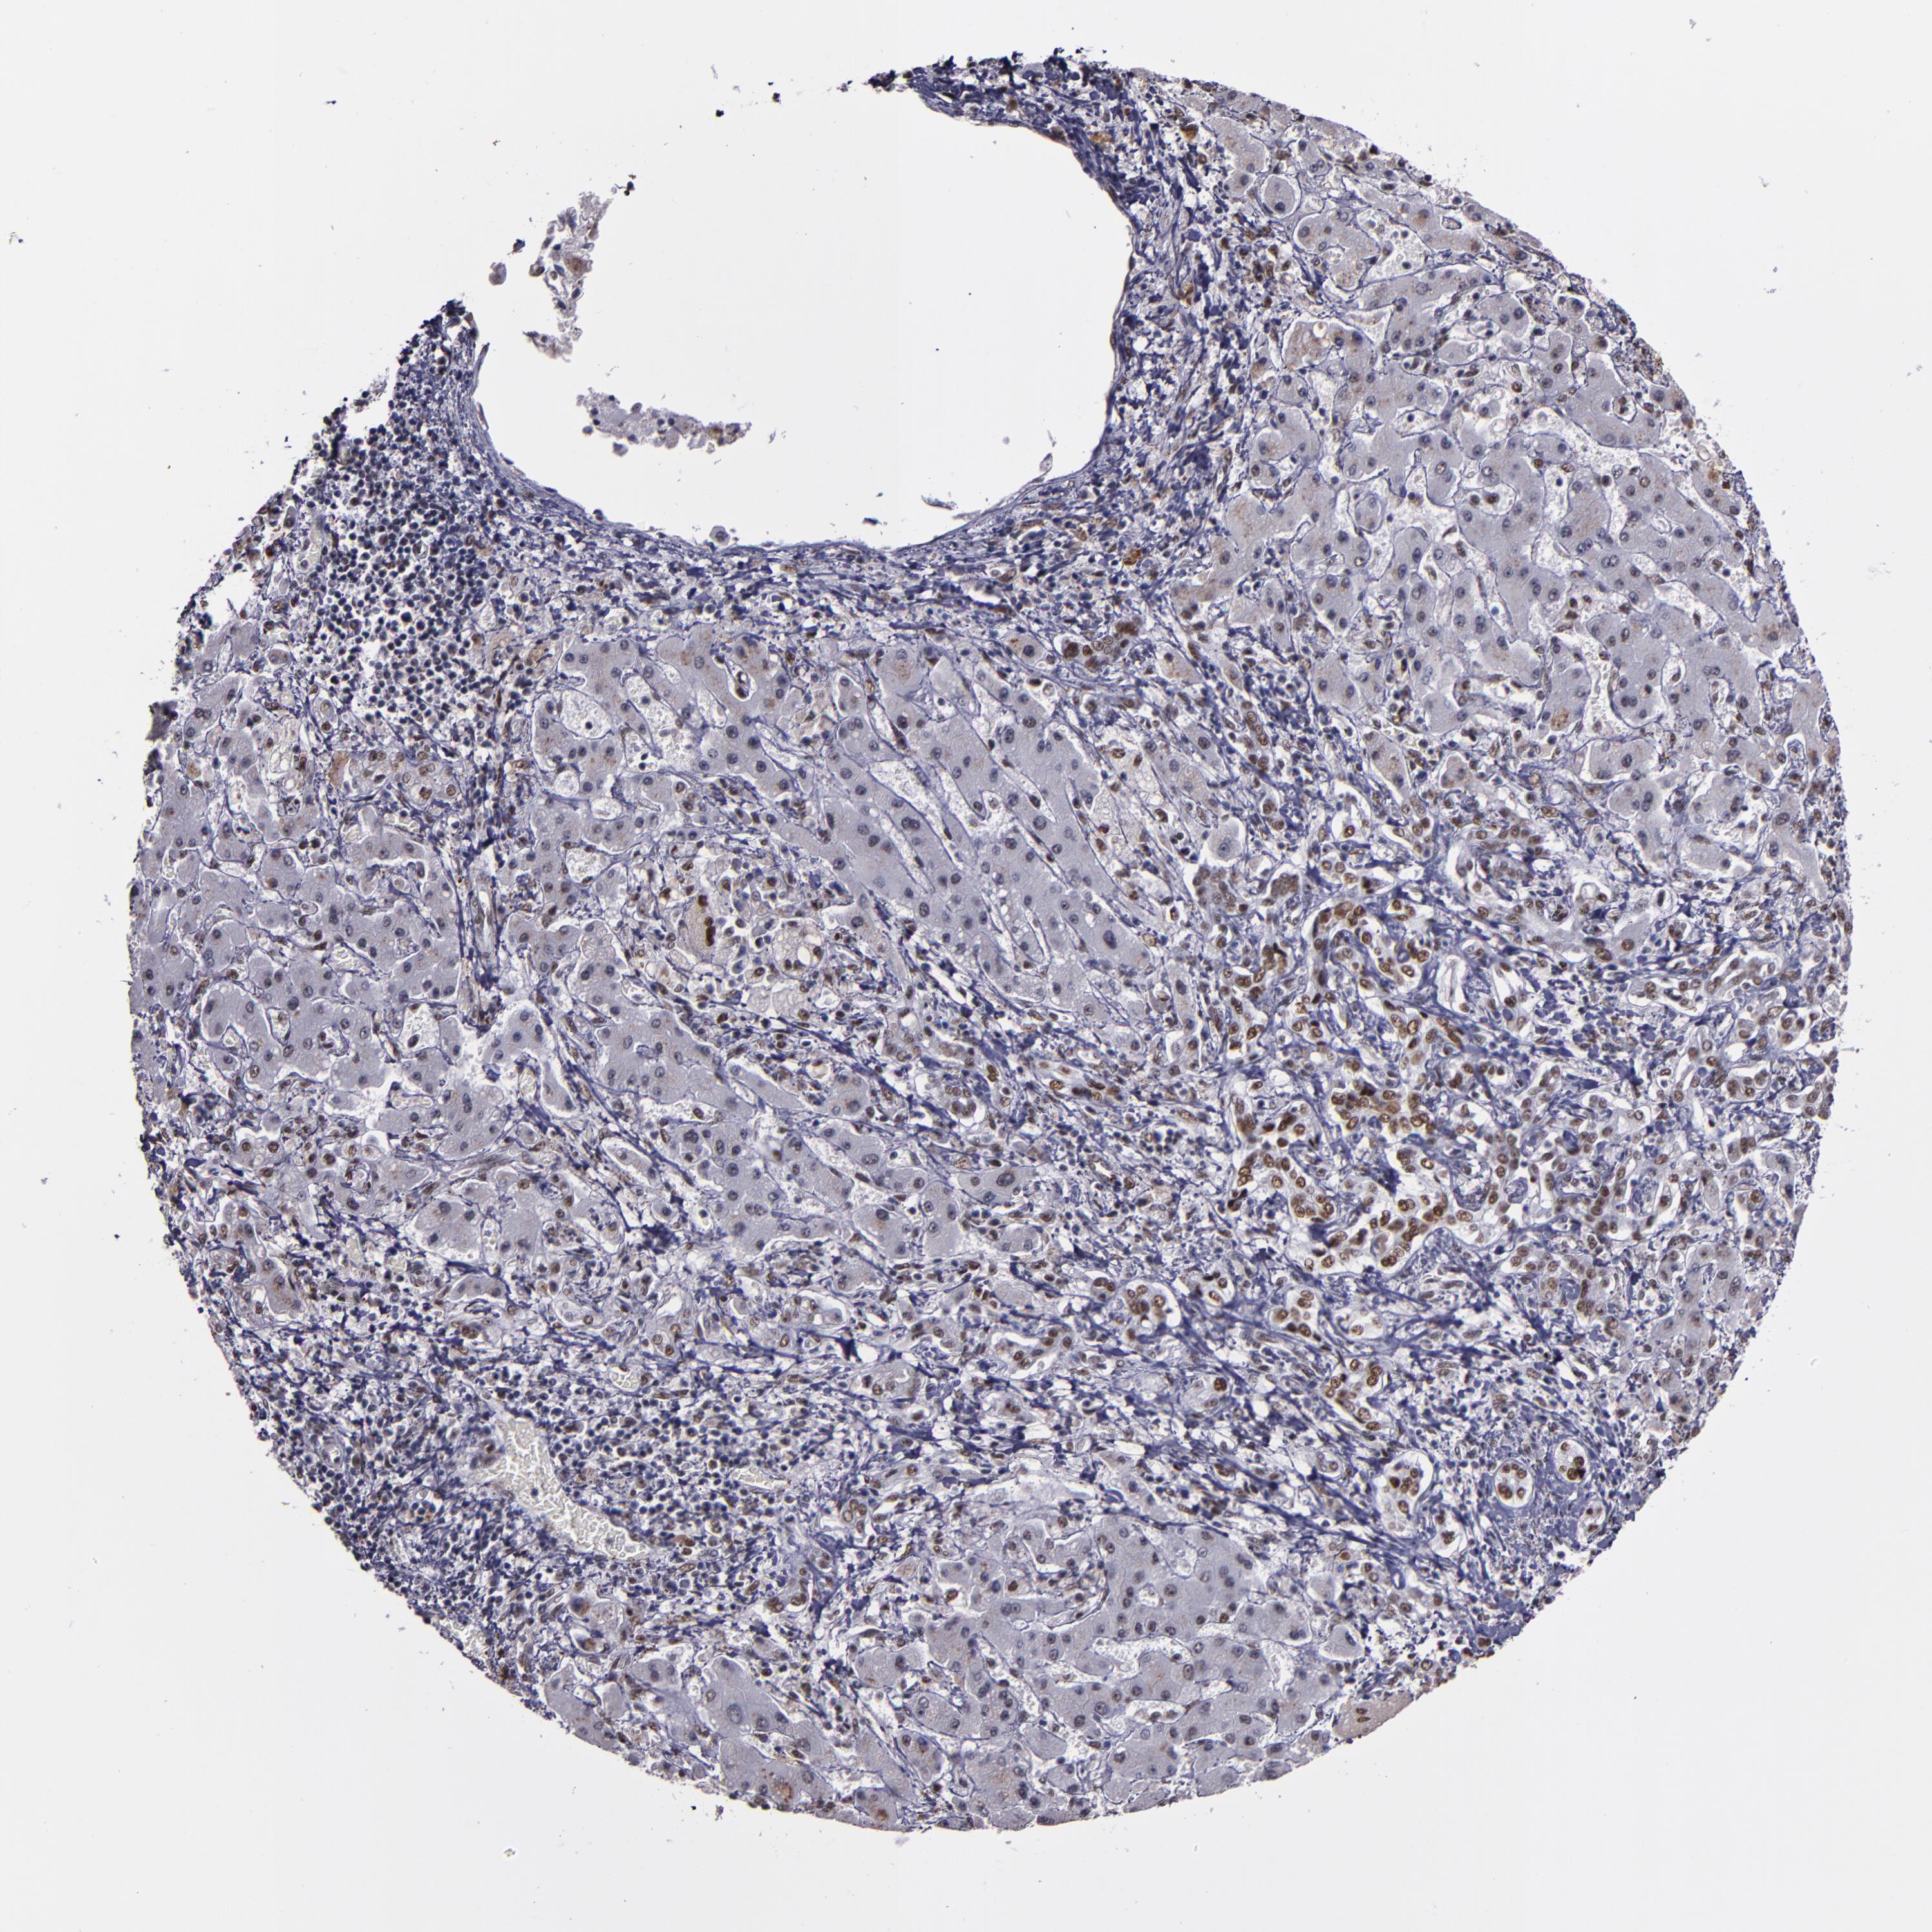

LIVER CANCER - Protein expressioni

A mouse-over function shows sample information and annotation data. Click on an image to view it in a full screen mode. Samples can be filtered based on level of antibody staining by selecting one or several of the following categories: high, medium, low and not detected. The assay and annotation is described here.

Note that samples used for immunohistochemistry by the Human Protein Atlas do not correspond to samples in the TCGA dataset.

Antibody stainingi

Antibody staining in the annotated cell types in the current human tissue is reported as not detected, low, medium, or high, based on conventional immunohistochemistry profiling in selected tissues. This score is based on the combination of the staining intensity and fraction of stained cells.

Each image is clickable and will lead to virtual microscopy that enables deeper exploration of all samples and also displays staining intensity scores, fraction scores and subcellular localization as well as patient and tissue information for each sample.

Antibody HPA002568

Staining

High

Medium

Low

Not detected

Intensity

Strong

Moderate

Weak

Negative

Quantity

>75%

75%-25%

<25%

None

Location

Nuclear

Cytoplasmic/membranous

Cytoplasmic/membranous,nuclear

Cholangiocarcinoma

Carcinoma, Hepatocellular, NOS